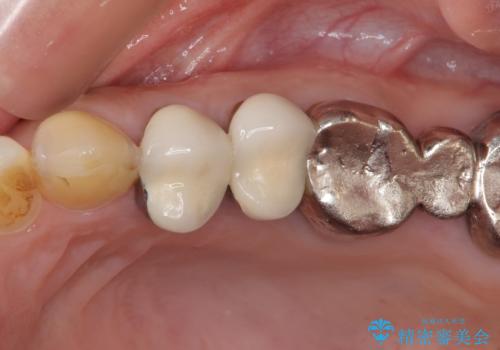

仮歯に変えた後にオールセラミッククラウンにて補綴することとしました。

治療前と比べてとても自然な前歯となり、患者様には大変満足していただきました。